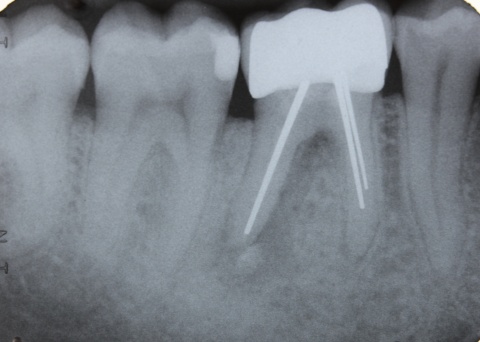

Dem Behandler kommt die Aufgabe zu, behandlungsbedingte Fehlerquellen möglichst auszuschalten. Eine solche kann die Ausdehnung der Trepanationsöffnung sein. Weitestgehend bekannt ist, dass ein gradliniger Zugang zu den Wurzelkanälen geschaffen werden sollte. Dieser technisch einfach umzusetzende Behandlungsschritt hilft den mechanischen „Stress“ durch Torsion auf die NiTi-Feilen deutlich zu verringern. Klinisch werden in nicht seltenen Fällen jedoch deutlich unterdimensionierte Trepanationsöffnungen oder persistierende Überhänge vorgefunden, welche die Belastung auf die Feilen unnötig erhöhen. Aufgrund stetig verbesserter technischer Möglichkeiten, wie beispielsweise die Anwendung hochauflösender Operationsmikroskope sowie der Ultraschalltechnologie, zieht heutzutage allerdings die Fraktur einer Feile selten die sofortige Extraktion nach sich. Sehr häufig ist die orthograde, bei ungünstiger Lage des Fragments seltener die retrograde, Entfernung möglich. Unter besonderen Voraussetzungen bei gleichzeitigem Abwägen des Risiko-/Nutzenverhältnisses ist auch das Belassen des separierten Instruments als praktikable Lösung möglich (Abb. 9 und 10).